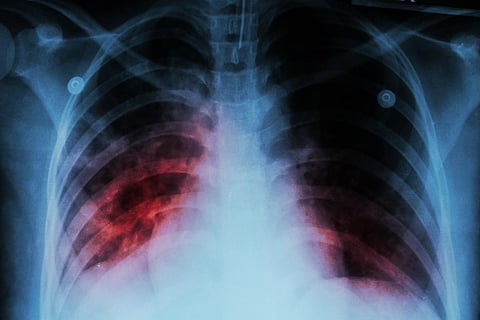

La tuberculosis es causada por bacterias transportadas por el aire que atacan principalmente los pulmones. Se estima que aproximadamente una cuarta parte de la población mundial tiene tuberculosis, pero solo entre el 5% y el 10% de ellos desarrollan síntomas, dijo la OMS.

Los síntomas que presentan las personas dependen de la parte del cuerpo afectada por la tuberculosis. Aunque por lo general ataca a los pulmones, también puede dañar los riñones, el cerebro, la columna vertebral y la piel, añadió la OMS.